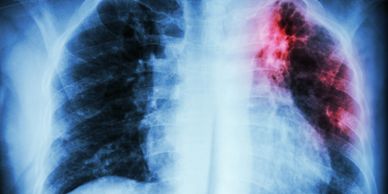

Chest X-ray showing lung infection with highlighted inflammation in the upper right lung.

La tuberculosis es causada por una bacteria llamada Mycobacterium tuberculosis se transmite por vía aérea al estar cerca de personas infectadas, inicia como un cuadro de tos persistente, a la que se le agrega fiebre y en ocasiones perdida de peso son los síntomas principales, el mas característico de ellos es la hemoptisis que es a como se le llama escupir sangre.  El estado de Nuevo Leon esta dentro de los estados de la republica con mas incidencia de esta enfermedad que se puede controlar si detecta a tiempo.